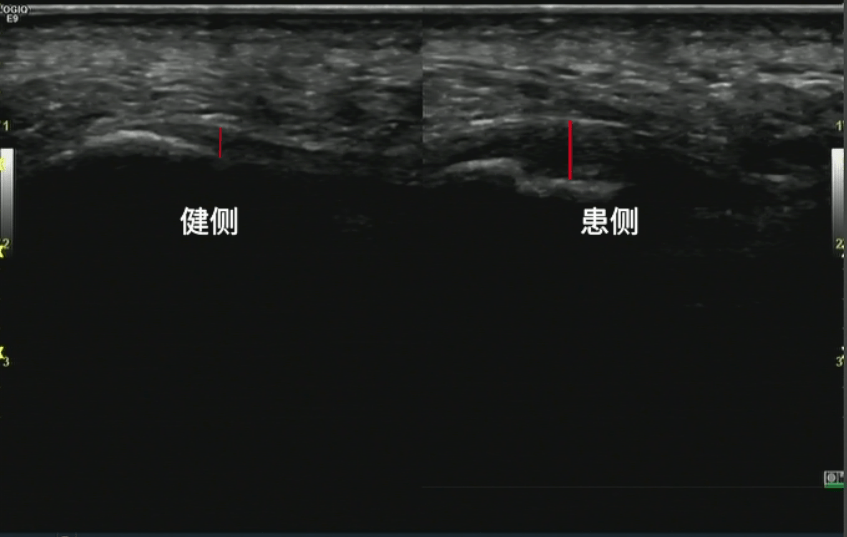

景长轴成像,b短轴成像,c双侧对比扫查,显示跟腱肿胀,浅方肌腱局部撕裂

图片尺寸1366x856